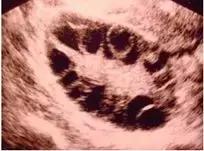

B超可以发现以下疾病:

各个部位的子宫肌瘤

卵巢多囊样改变